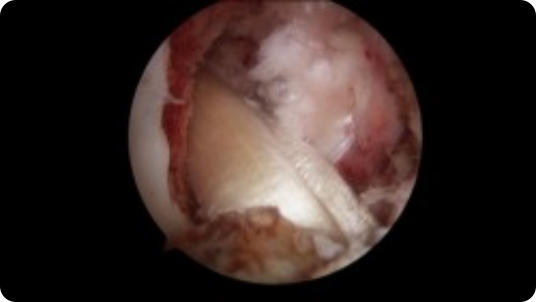

Arthroscopic image of a shoulder dislocation Arthroscopic image of a repaired shoulder dislocation

Shoulder Dislocation

Shoulder Dislocation Repair